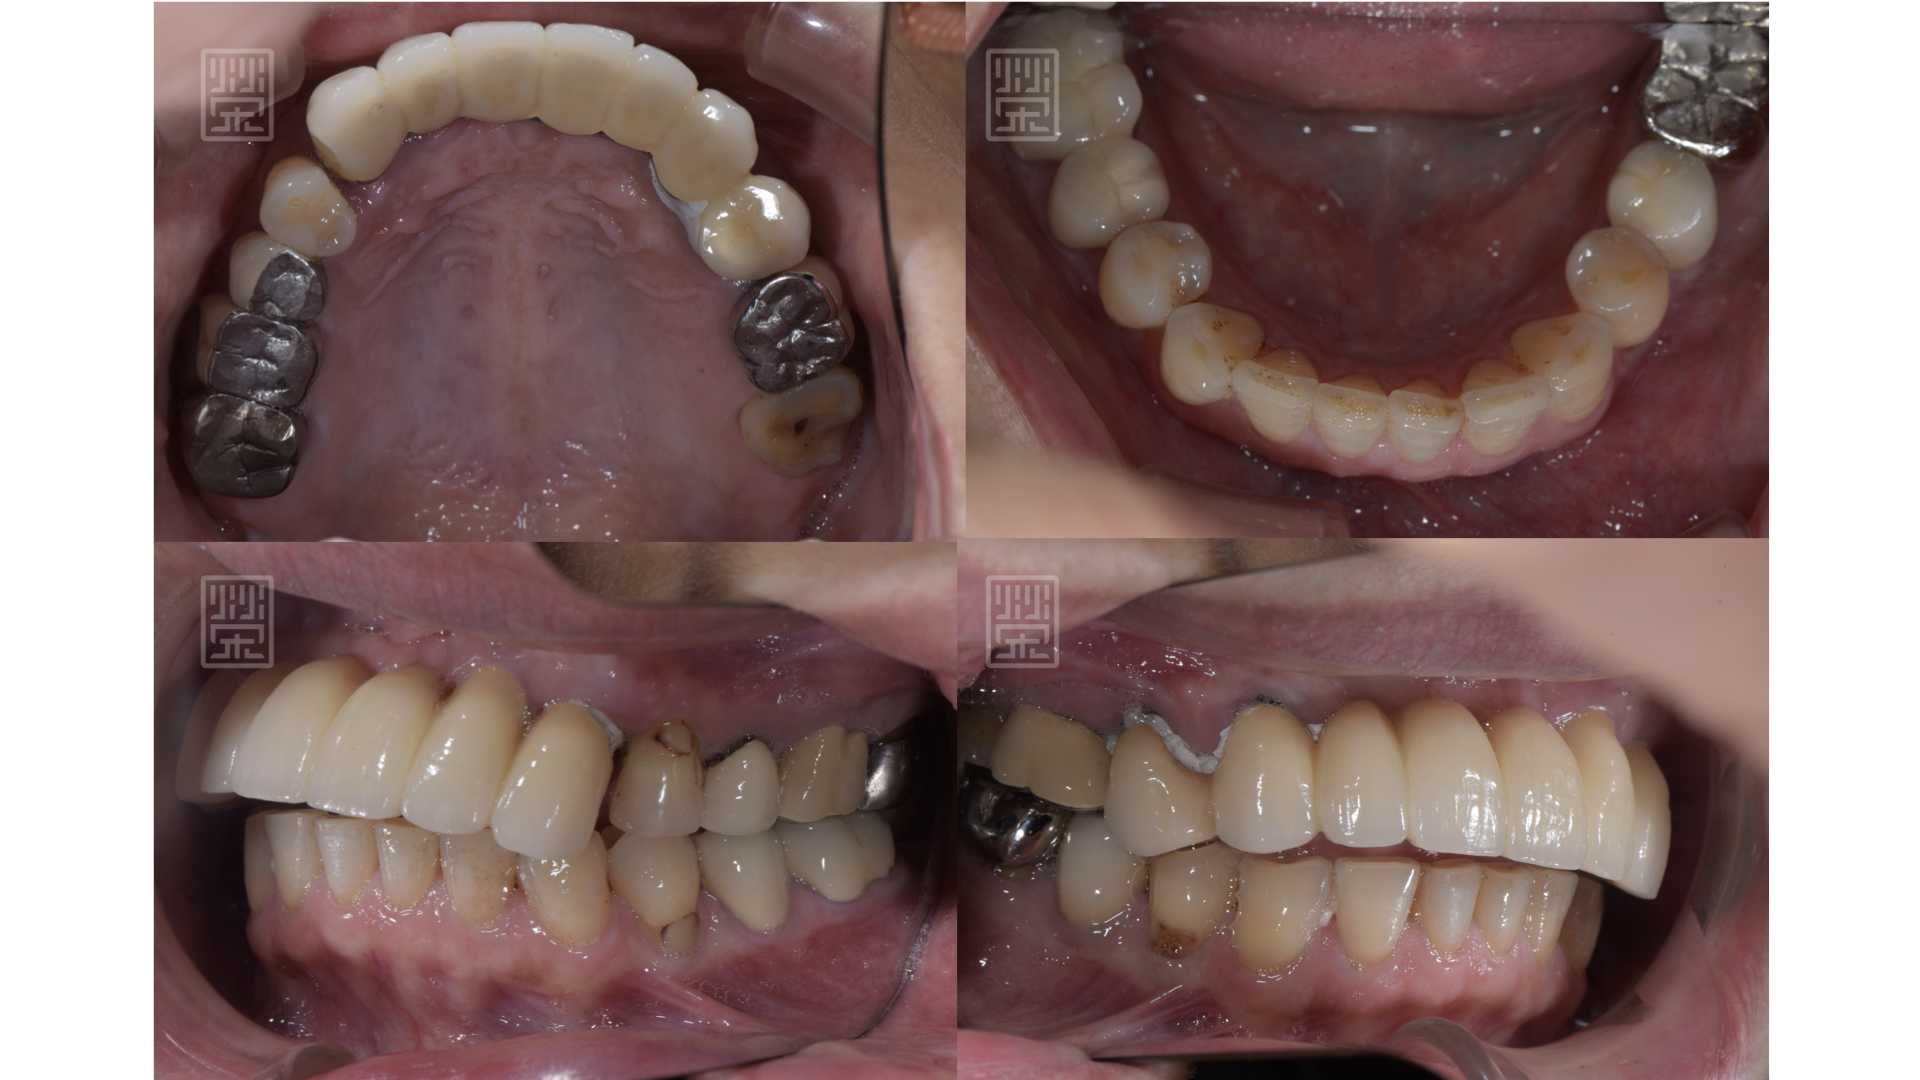

更換臨時假牙後,恢復外觀與功能

預計增加上顎門牙長度,先將下顎門牙用樹脂恢復原本型態,將貼片的空間先保存起來

藉由矯正,將下顎們牙齒軸拉正